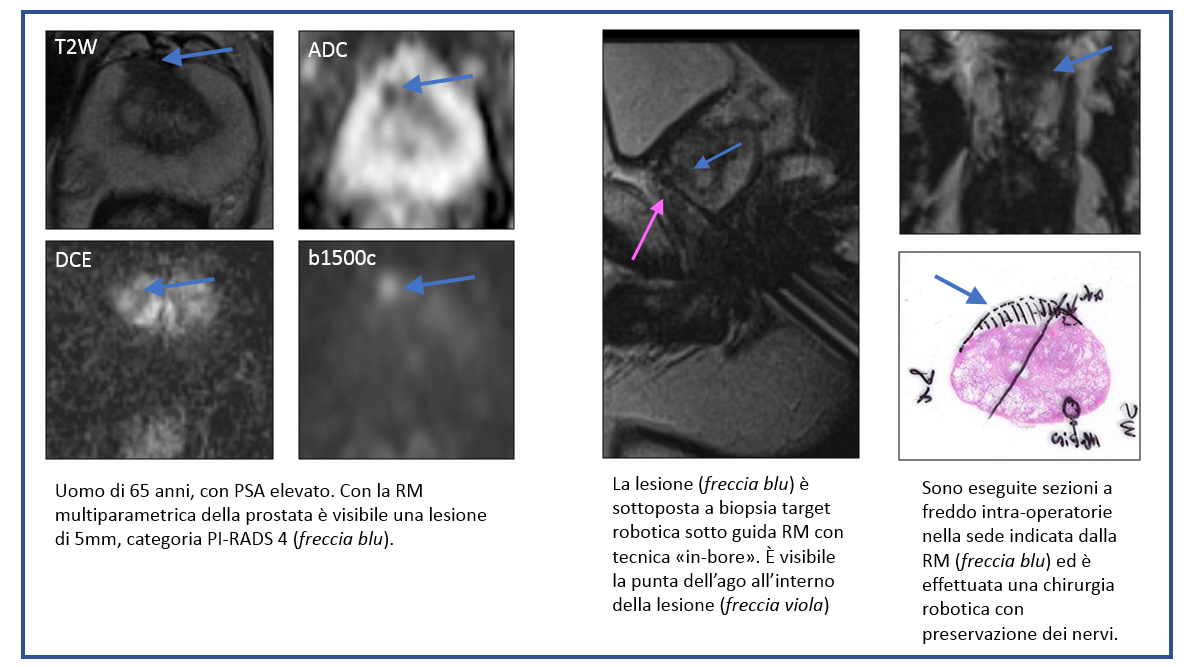

Imaging di precisione: caso 1

L’imaging di precisione con RM multiparametrica della prostata ha permesso di individuare un piccolo tumore prostatico (5mm) e di sottoporlo a biopsia target robotica sotto guida RM con tecnica “in-bore”. Grazie alla esatta localizzazione del tumore, è stato possibile eseguire sezioni a freddo intra-operatorie ed effettuare una chirurgia robotica con preservazione bilaterale dei nervi, con margini chirurgici negativi. Il paziente ha così potuto evitare terapie mediche e radioterapia, con buon recupero funzionale di continenza e potenza sessuale.